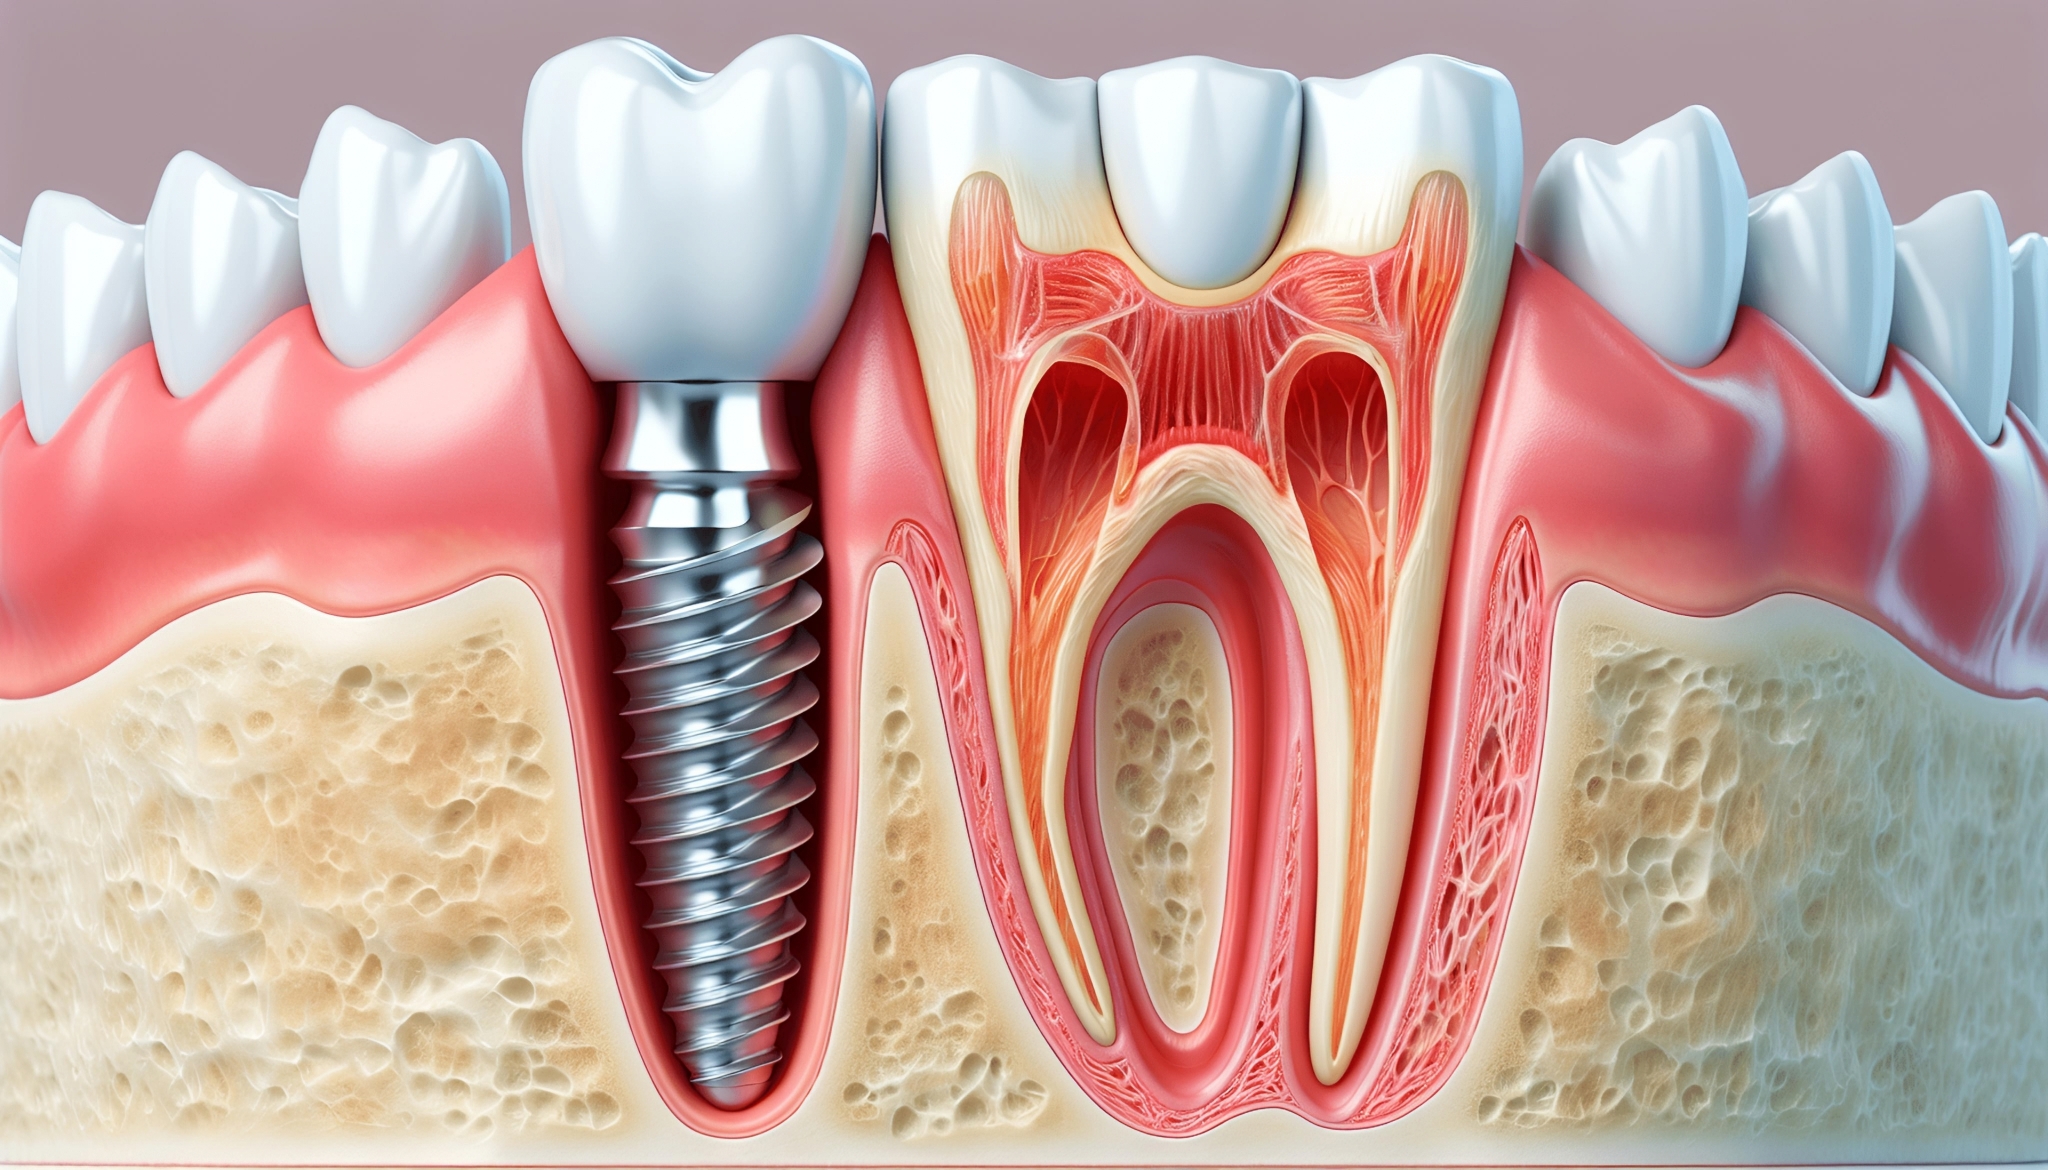

برخی از افراد به دلایل مختلف ممکن است دندانهای خود را از دست بدهند. همانطور که در تصویر بالا نشان داده شده، ایمپلنت دندان یا فیکسچر به اندازه ریشه دندان فرد، بهجای ریشه از دست رفته قرار میگیرد. فیکسچرها قطعاتی هستند که به اندازه دندان طبیعی ساخته میشوند و با دقت بالا طراحی میشوند تا بهطور کاملاً طبیعی به نظر برسند.

ایمپلنت دندان از دو قسمت اصلی تشکیل میشود فیکسچر (Fixture) و اباتمنت (Abutment). قسمتی که در داخل استخوان فک قرار میگیرد، فیکسچر نام دارد و قسمتی که بالای لثه قرار میگیرد، اباتمنت نامیده میشود. روی اباتمنت، پروتز یا روکش ایمپلنت نصب میشود. پایه ایمپلنت معمولاً از تیتانیوم ساخته میشود زیرا تیتانیوم بهدلیل سازگاری بسیار خوب با استخوان فک، از ایجاد مشکلاتی مانند لغزش، سر و صدا یا آسیب به استخوان جلوگیری میکند.